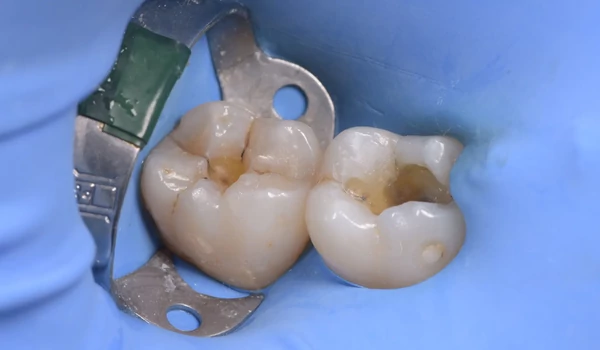

4. ábra Tömési eljárás: A folyékony kompozit első rétegének felvitele. |

5. ábra A második őrlőfog már tömve van, az elsőre egy újabb réteg folyékony kompozitra van szükség. |